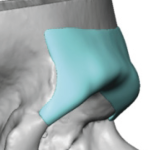

“Aesthetic temporal reduction” (often called temporal narrowing surgery) is a niche craniofacial procedure aimed at reducing the width of the head in the temple region (the area above and slightly behind the eyes). What it targets The temporal region (sides of the skull) Specifically: Temporal bone (outer skull) Temporalis muscle (a chewing muscle that can add bulk) How it’s done Read More…